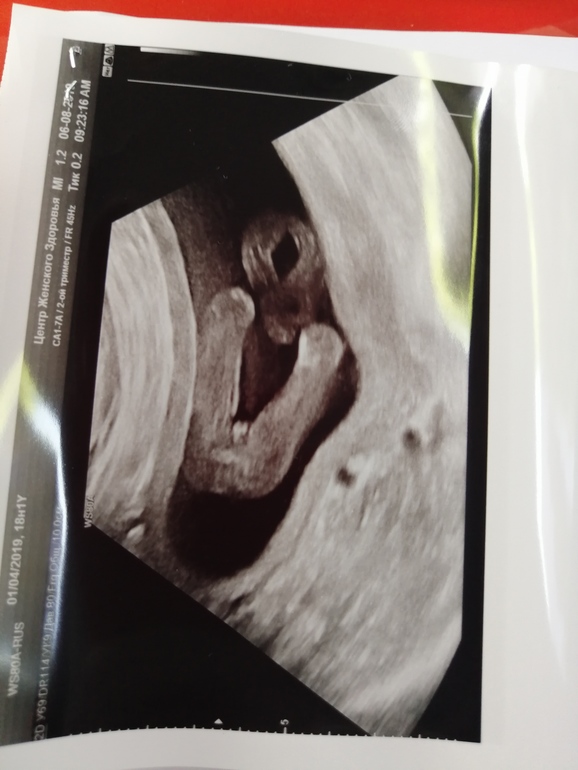

ДЕВОЧКА!!!! 🥰🥰🥰 Узи 17 неделек)

УЗИ, КТГ, доплерМоя принцесса, моя радость!!!! 🥰🥰🥰

Всё у нас хорошо, 176 гр весит моя кроха!!! 🥰🥰🥰

И шейка 46!!!каким чудом она такой стала, буду верить, что и дальше все будет хорошо!!!! 🥰🥰🥰

Я с самого первого УЗИ не сомневалась, что Девочка. Теперь поздравляю, что уже точно 100% подтвердилась!!! Я на фото УЗИ обычно ничего не понимаю, а тут всё так хорошо видно ))) Замечательно, что шейка в порядке. Пусть так будет и дальше!